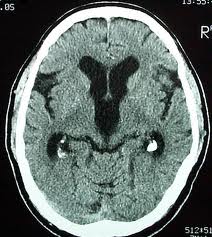

Pada bulan Desember 2012 ini, saya mendapatkan kehormatan dengan diundang untuk melakukan tindakan kateterisasi otak atau yang disebut dengan “Endovascular Neurosurgery / Neuro Intervensi” di kota Medan. Tindakan ini merupakan kekhususan keilmuan bedah saraf yang sempat saya pelajari di Jepang pada tahun 2011. Saya mendapatkan undangan dari seorang dokter spesialis bedah saraf disana, Dr. dr. Ridha Dharmajaya, SpBS, dimana beliau juga adalah senior saya selama menjalani pendidikan bedah saraf di Departemen Bedah Saraf FKUI-RSCM dulu. Sebanyak 7 pasien dapat beliau kumpulkan dan terima untuk menjalani tindakan kateterisasi otak tersebut. Sebagian besar dari pasien-pasien tersebut datang dengan keluhan kelumpuhan akibat serangan stroke yang sudah diderita beberapa hari hingga beberapa minggu sebelumnya. Keluhannya bervariatif namun sebagian besar datang dengan kelumpuhan satu sisi tangan dan kaki. Ada juga dengan keluhan sulit berbicara hingga “cadel”. Tindakan kateterisasi ini saya tujukan untuk melihat dengan jelas struktur pembuluh darah otak dan mencari pembuluh darah otak yang mengalami sumbatan tersebut.

Alhamdulillah, 7 kasus tersebut dapat diselesaikan dalam 1 hari tanpa ada halangan yang berarti, dan kita dapat menemukan lokasi-lokasi tersumbatnya pembuluh-pembuluh darah tersebut. Hampir seluruh kasus menunjukkan kelainan yang nyata yang terlihat dengan jelas sekali dari tindakan angiografi/kateterisasi yang kita lakukan. Dengan diketahui secara jelas lokasi dan jenis gangguan yang mengakibatkan hambatan aliran darah ke jaringan otak maka saya dapat memberikan rekomendasikan tindakan atau tatalaksana selanjutnya yang sebaiknya dilakukan. Pilihan memang terbuka antara tindakan operasi membuang “plaque” di dalam pembuluh darah atau tindakan pemasangan stent dengan tujuan memperlebar pembuluh darah yang menyempit atau tertutup tersebut.

Saya tetap memotivasi dan menyarankan kepada seluruh masyarakat Indonesia untuk melakukan “screening” pembuluh darah otak, khususnya bila telah memiliki faktor resiko kemungkinan sumbatan seperti adanya penyakit tekanan darah tinggi, penyakit gula, penyakit kadar kolesterol yang tinggi, penyakit jantung, obesitas dan tentunya faktor usia. Dengan tindakan “angiografi/kateterisasi otak” kita dapat memeriksa dan mengetahui pembukuh darah mana yang merupakan calon untuk mengalami sumbatan atau calon untuk pecah. Cegahlah sebelum terjadi penyumbatan atau pecahnya pembuluh darah tersebut. Cegahlah stroke dan selamatkan produktifitas anda semua.